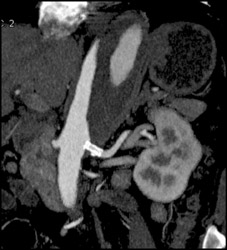

Aortic Dissection